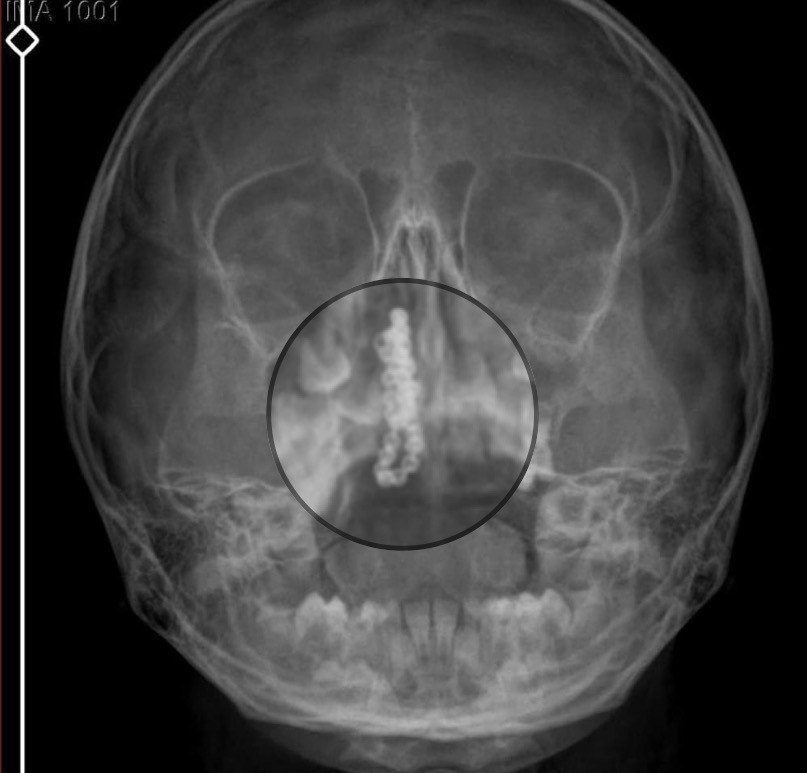

Kentte yaşayan Gökhan-Nalan Tekin çifti, yaklaşık 4 ay önce şiddetli burun kanamasının yanı sıra akıntı şikayetleriyle kızları Polen'i, bir özel hastaneye götürdü. Burada röntgeni çekilip, tetkikleri tamamlanan küçük kıza, iddiaya göre enfeksiyon teşhisi konulup, ilaç verildi. Eve dönen aile, kanama ve akıntının geçmemesi üzerine bu kez Rize Devlet Hastanesi'ne giderek Kulak Burun Boğaz Polikliniği'ne başvurdu. Devlet hastanesindeki doktorun incelemesi ve kapsamlı röntgen çekilmesi sonrası Polen'in burnunda metal cisim olduğu fark edildi. 2 yıldır burunda kaldığı değerlendirilip, küçük top şeklinde tırnak makası zinciri olduğu belirlenen cisim, başarılı ameliyatla çıkarıldı. Bir süre tedavisi sürdürülen Polen, sağlığına kavuşunca taburcu edildi. Özel hastane yetkilileri, konuyla ilgili açıklama yapmazken; aile suç duyurusunda bulunacaklarını söyledi.

Kızının burnundan sürekli siyah renkte akıntı olduğunu anlatan Gökhan Tekin, “Çocuğumun burnundan kanama ile sürekli siyah akıntı geliyordu. Özel hastaneye götürdüm. Özel hastanede film çekildi, hiçbir bulguya rastlanılmadığı söylendi. O siyah leke de enfeksiyona dayalı olan bir şey olduğu bize söylendi. Eve geldik, akıntı sürmesi üzerine bu kez devlet hastanesine başvurduk. Burunda metal zinciri fark ettiler. Böyle bir ihmalkarlık olabilir mi? Özel hastaneye gidiyoruz, paramızla rezil oluyoruz. Zincir, 2 yıldır burnunda ve devletimizin hastanesinde iyi bir doktorumuz zinciri ortaya çıkarıyor, kızım ölümden dönüyor. Ben sonuna kadar bu işin peşini bırakmayacağım. Sonuna kadar hukuk mücadelesi vereceğim. Bu da diğer hastalarımıza ibret olsun. İşte, bakın koca bir zincir. 'Bulguya rastlanılmadı' deniliyor” dedi.

Kızının ameliyat sonrası durumunun iyi olduğunu söyleyen Tekin, “İnanır mısınız bize 'Evde soba mı yanıyor? Acaba kömür isten dolayı mıdır bu?' dendi. Böyle bir şey olabilir mi? Ameliyattan çıkan parmağım kadar zincir. Devlet hastanesindeki doktor da 'Bu nasıl gözden kaçılabilir? Böyle bir pozisyon nasıl görülmeyebilir?' yorumunda bulundu. Allah'a şükür olsun atlattık. Şu anda durumu, vaziyeti iyidir. Ben şuna inanıyorum doktor da bir şans işidir. Bakın paramızla özele gideriz ya hani bizde, daha iyi ilgilenirler. Oysa devlet hastanesindeki doktorumuz olayı meydana çıkardı” diye konuştu.